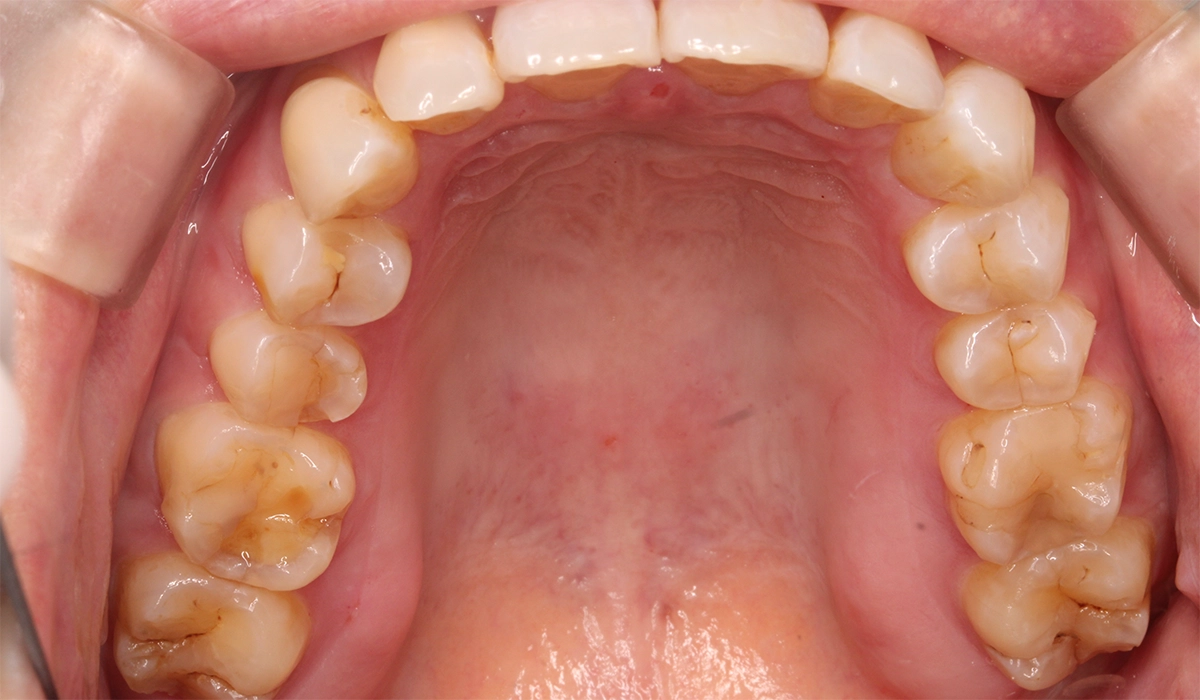

術前:上顎